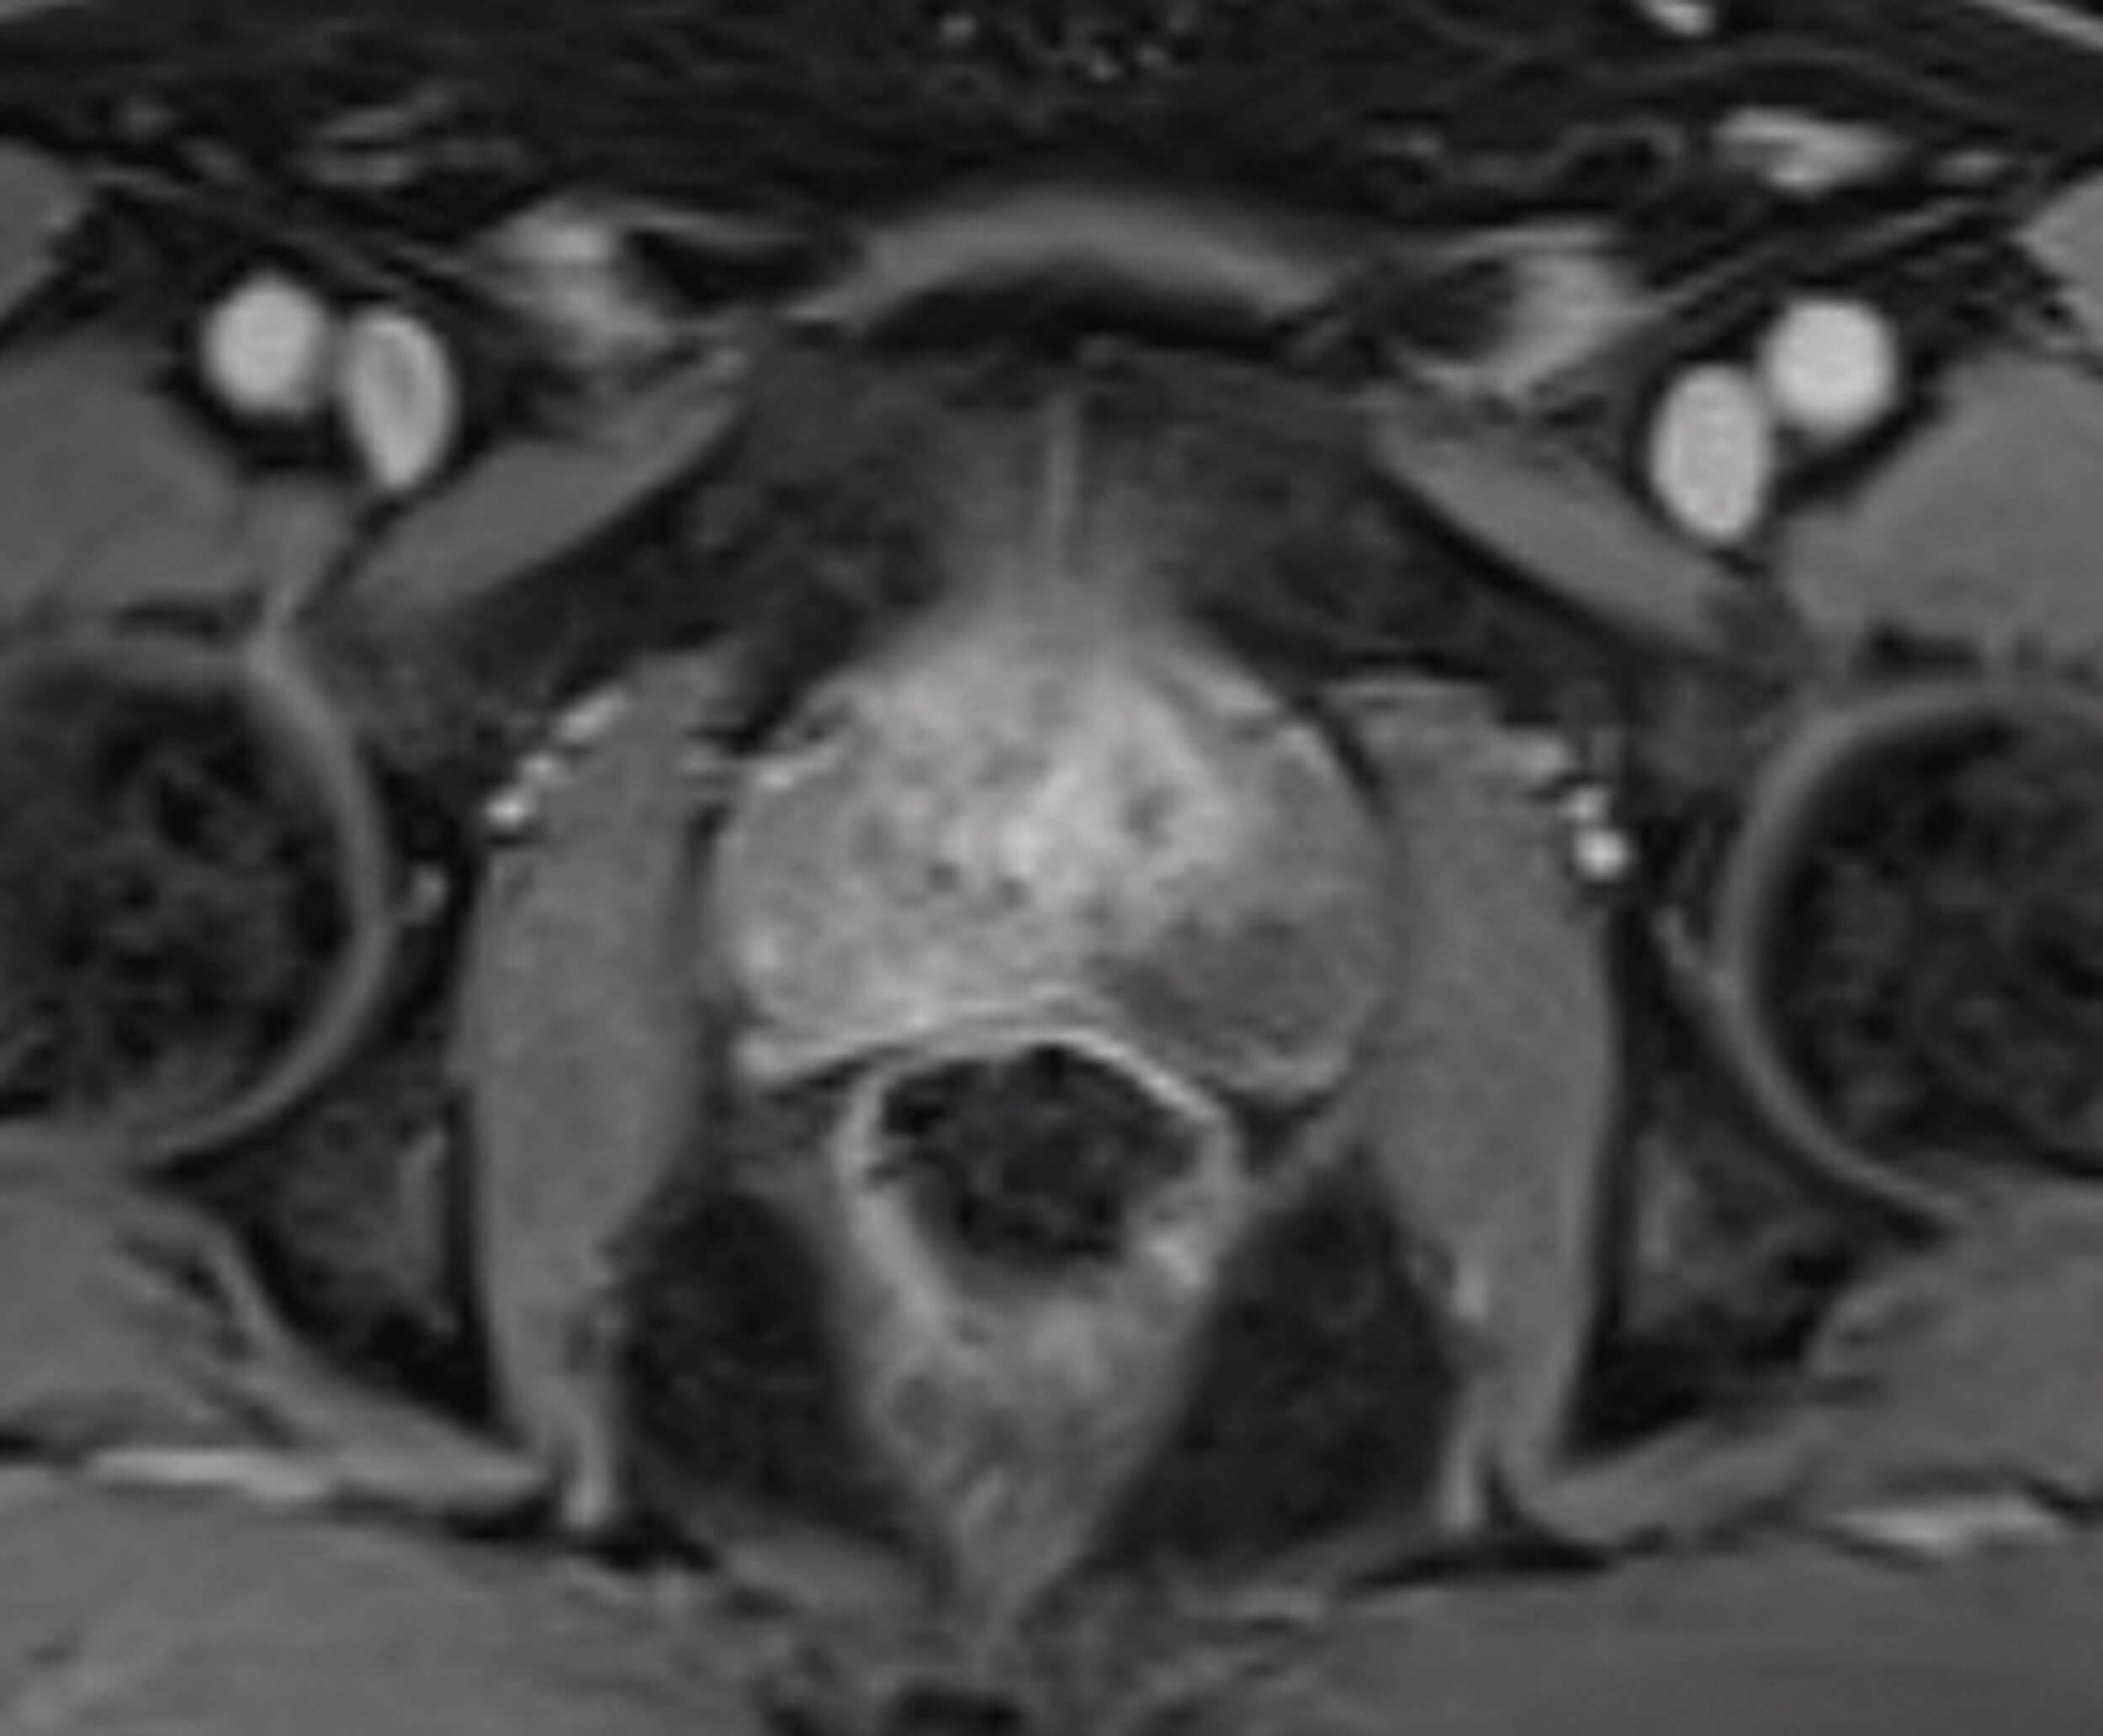

Figure 4 is the dynamic contrast enhancement (DCE) sequence post injection of IV gadolinium. Tumour neogenesis causes contrast stasis in tumour regions and appear as enhancement. Prostate cancer therefore appears brighter on DCE, as seen in the right peripheral zone.